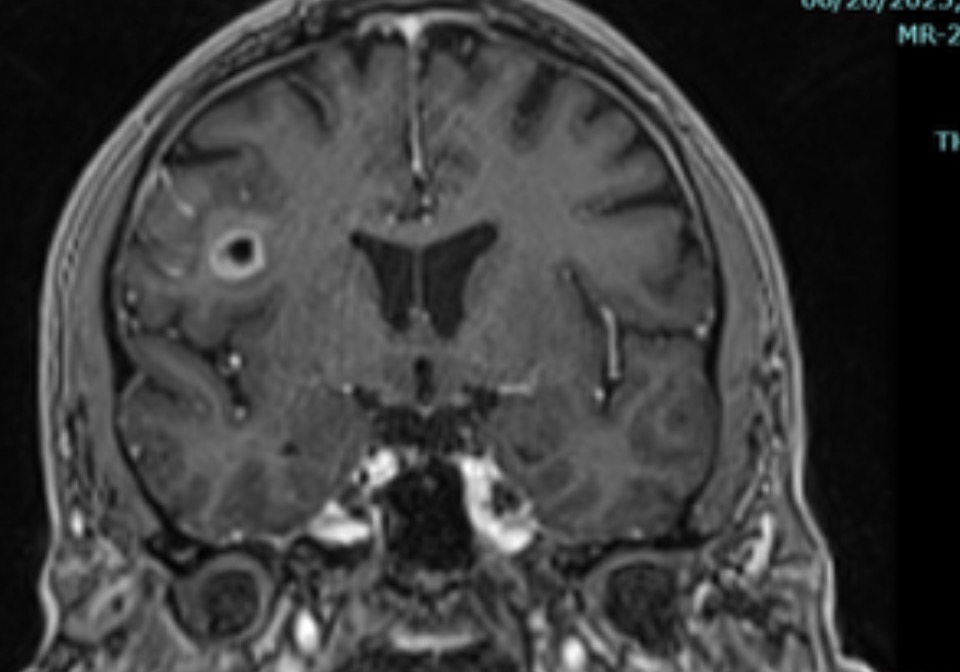

In April of 2025, Christian began experiencing seizures. Over the following months, things escalated: he's now had over 200 seizures and two strokes, leading to multiple physical injuries. On July 8th, 2025, Christian was diagnosed with Stage 4 Glioblastoma (GBM)—a rare, highly aggressive brain cancer that affects just 1% of men his age.

His first major brain surgery is Thursday, July 17th, 2025. Doctors have given him a prognosis of just 9-14 months, *if* he survives the surgery and endures a difficult course of chemo and radiation. His medical bills have already surpassed $400,000, and the financial burden is overwhelming.